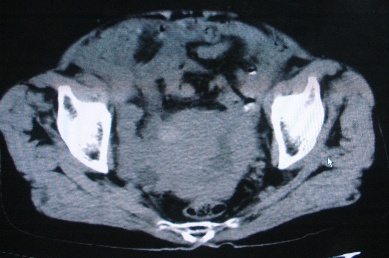

以下是引用卜一在2007-4-30 15:29:00的发言:[br]子宫明显增大,不规则,子宫壁不规则增厚,子宫腔明显缩小,子宫右侧软组织团块与子宫关系密切,内见低密度坏死区。考虑:子宫癌并周围侵润。